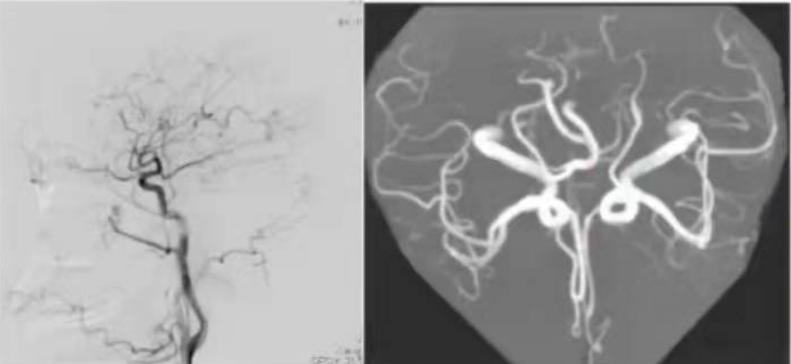

我们再看一下该患者的DSA及MRA:

图7:DSA和MRA备注(图中红色箭头所指为左侧胚胎型大脑后动脉)患者存在左侧胚胎型大脑后动脉,考虑责任血管为左侧颈内动脉。那么,该青年患者出现颈内动脉夹层的病因是什么呢?